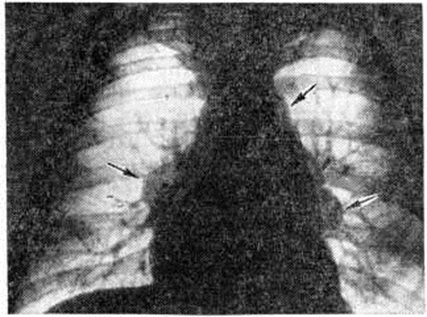

Поражение слизистых оболочек может быть изолированным, но чаще сочетается с саркоидами кожи. На миндалинах, мягком и твёрдом небе, языке обнаруживаются плотные опаловые узелки, окружённые гиперемическим ободком, или бледно-жёлтые бляшки, иногда гипертрофированные или изъязвлённые. Осложнения обычно связаны с прогрессированием лёгочного процесса — развитием бронхообтурационного синдрома, эмфиземы лёгких (смотри полный свод знаний), дыхательной недостаточности (смотри полный свод знаний), лёгочного сердца (смотри полный свод знаний), сердечной недостаточности (смотри полный свод знаний), реже с возникновением хронический почечной недостаточности (смотри полный свод знаний). Поражение глаз может привести к вторичной глаукоме (смотри полный свод знаний), катаракте (смотри полный свод знаний), снижению зрения вплоть до полной слепоты. Диагноз ставят на основании тщательного анализа анамнестических и клинико-рентгенол. данных, результатов поиска микобактерий туберкулёза, определения уровня кальциемии и кальциурии, отрицательных результатов реакции на туберкулин, а также других иммуно л. тестов, выявляющих угнетение клеточного иммунитета: реакции бластотрансформации лимфоцитов (смотри полный свод знаний) с фитогемагглютинином, спонтанного розеткообразования (смотри полный свод знаний: Розеткообразования тесты), торможения миграции лейкоцитов (эти реакции изучают также после подкожного введения туберкулина). Важное значение в диагностике Саркоидоз имеет гистологический или цитологический исследование поражённых тканей. Объектом для такого исследования может быть кожа, увеличенный лимфатических, узел, ткань лёгкого. Материал для биопсии (смотри полный свод знаний) получают при медиастиноскопии, бронхоскопии с трансбронхиальной пункцией узла, реже приходится прибегать к закрытой или открытой пункции лёгкого. Определённую помощь в диагностике Саркоидоз может оказать проба Квейма, которая, по некоторым данным, оказывается положительной в большинстве случаев Саркоидоз, по другим — у 50— 70% больных. Пробу выполняют путём внутрикожного введения 0,1 — 0,2 миллилитров специфического антигена, полученного из саркоидной ткани больного. Через 2—3 недель на месте инъекции появляется багрово-красный узелок, который ещё через 2—3 недель подвергают биопсии. Пробу считают положительной, если в биопсийном материале обнаруживают изменения, характерные для Саркоидоз Использование пробы ограничено из-за отсутствия стандартного антигена (отсюда, повидимому, и противоречия в оценке её диагностической ценности), а также отсроченности её результатов. Такие изменения, как моноцитоз, умеренная лейкопения, лимфопения, палочкоядерный сдвиг, ускорение РОЭ, имеют значение в оценке активности процесса. Для диагностики Саркоидоз глаза проводят многостороннее офтальмологический обследование больного с учётом признаков поражения других органов и систем. Диагноз Саркоидоз кожи ставят на основании исследования высыпаний, результатов диаскопии и гистологический исследования. Диагностика внутригрудного Саркоидоз в ряде случаев весьма затруднена и иногда требует пункционной биопсии лёгкого, чаще трансбронхиальной биопсии лёгкого (смотри полный свод знаний: Бронхоскопия, Бронхофиброскопия). В случае Саркоидоз бронхов бронхоскопия может иметь решающее значение для постановки диагноза. Рентгенодиагностика имеет особенно важное значение для распознавания внутригрудных форм Саркоидоз (нередко определяя первичный диагноз ещё до появления явных клинические, симптомов) и помогает при установлении диагноза в случае характерных поражений костной системы. При обследовании больных, помимо обзорной рентгенографии, используют томографию лёгких и средостения (смотри полный свод знаний: Томография)i; по показаниям применяют бронхографию (смотри полный свод знаний) и пневмомедиастинографию (смотри полный свод знаний). При I стадии Саркоидоз органов дыхания рентгенологически определяется расширение корней лёгких и средостения за счёт опухолевидного увеличения всех групп лимфатических, узлов грудной полости, преимущественно лимфатических узлов корней лёгких. Очертания корней лёгких и средостения имеют полициклический характер, тени передних и задних групп лимфатических, узлов средостения, накладываясь друг на друга, создают симптом «кулис», увеличение лимфатических, узлов средостения из-за суммации теней придаёт сердцу митральную конфигурацию (рисунок 6). На томограммах выявляется, что увеличенные лимфатических, узлы располагаются по окружности крупных бронхов в области их деления на долевые, сегментарные и субсегментарные ветви. Иногда лимфатических, узлы образуют дугообразные вдавления стенок бронхов, в ряде случаев ведут к нарушениям бронхиальной проходимости — образуются участки гиповентиляции, ателектаза. Для II стадии характерна картина очаговой диссеминации: определяется избыточный, петлистый рисунок в прикорневых и нижних отделах лёгких (стадия IIа), образование мелких (милиарных) очагов (стадия IIб), появление более крупных очагов диаметром 3 — 5 миллиметров (стадия IIв), формирование крупных очагов диаметром более 6 миллиметров (стадия IIг). Наиболее постоянным является сочетание интерстициальных изменений с очаговыми, занимающими преимущественно прикорневые отделы средних и нижних лёгочных полей (рисунок 7). III стадия характеризуется наличием распространённого фиброза, участков цирроза лёгких (рисунок 8). В некоторых случаях встречаются атипичные проявления Саркоидоз: одностороннее увеличение лимфатических, узлов, односторонняя диссеминация, наличие в лёгких одиночных или нескольких фокусов уплотнений, локализованное скопление очагов в пределах одного сегмента лёгкого. К атипичным относится также преимущественно верхушечная локализация очагов, более характерная для туберкулёза. Облегчить диагностику Саркоидоз может рентгенологическое обнаружение характерных изменений в скелете. В эпифизах фаланг кистей рук и в костях, образующих лучезапястные и коленные суставы, определяются одиночные или множественные округлые просветления диаметром 4 — 10 миллиметров со склеротическим ободком; реже костные изменения имеют разлитой характер. Дифференциальную диагностику до обнаружения характерных для Саркоидоз гранулем в биопсийном материале приходится проводить с многими заболеваниями, особенно системного характера. Внутригрудную форму Саркоидоз в I стадии процесса приходится дифференцировать с туберкулёзом внутригрудных лимфатических, узлов, медиастинальной формой лимфогранулематоза, во II — III стадиях — с диссеминированным туберкулёзом лёгких (смотри полный свод знаний: Туберкулёз органов дыхания), карциноматозом, хронический воспалительными лёгочными заболеваниями, пневмокониозами (смотри полный свод знаний), реже другими лёгочными диссеминированными поражениями. Рентгенологически при туберкулёзном бронхадените (смотри полный свод знаний) в отличие от Саркоидоз наблюдается преимущественно одностороннее увеличение лимфатических, узлов, они спаяны, очертания корня лёгкого бугристые. При лимфогранулематозе (смотри полный свод знаний) увеличение лимфатических, узлов достигает значительной степени, имеет асимметричный характер, часто преобладает увеличение лимфатических узлов средостения. Саркоидоз глаза дифференцируют с вялотекущими формами иридоциклита (смотри полный свод знаний) туберкулёзной или герпетической этиологии. Саркоидоз кожи дифференцируют с кольцевидной гранулемой (смотри полный свод знаний: Гранулема кольцевидная), лимфоцитомой кожи (смотри полный свод знаний), туберкулёзом кожи (смотри полный свод знаний: Туберкулёз внелёгочный), красными угрями (смотри полный свод знаний: Угри), гранулемой лица с эозинофилией (смотри полный свод знаний: Гранулема лица), красным плоским лишаем (смотри полный свод знаний: Лишай красный плоский), гемодермиями (смотри полный свод знаний). Лечение саркоидоза в случае развития осложнений комплексное, включает различные симптоматические средства и методы вплоть до оперативного лечения осложнений (при Саркоидоз глаза) в сочетании с патогенетической терапией глюкокортикоидами. По данным З. И. Костиной с соавторами (1981), на фоне лечения глюкокортикоидными гормонами (смотри полный свод знаний) прогрессирование заболевания и его рецидивы наблюдаются в 3 раза реже, чем без лечения. Поэтому глюкокортикоидная терапия считается целесообразной при всех формах и стадиях Саркоидоз, если на протяжении 3—5 месяцев динамического наблюдения не обнаруживается тенденции к спонтанной регрессии процесса. Если же заболевание отчётливо прогрессирует, лечение следует начинать незамедлительно. А. Е. Рабухин и соавторами (1975) рекомендуют следующую схему гормональной терапии: преднизолон в суточной дозе 30 миллиграмм в течение 1-го месяца, в дозе 25 миллиграмм на протяжении 2-го месяца, в дозе 20 миллиграмм в течение 3-го, а затем каждые 2— 3 недель дозу снижают на 2,5 миллиграмм. В поддерживающей дозе 7,5—5 миллиграмм терапию продолжают 6 месяцев и более. Можно применять другие глюкокортикоидные гормоны в эквивалентных дозах. При саркоидозе глаза преднизолон или дексаметазон назначают местно в виде подконъюнктивальных или ретробульбарных инъекций. Некоторые специалисты рекомендуют сочетать гормональную терапию с назначением противотуберкулёзных средств (смотри полный свод знаний), например, тубазида в дозе 10 миллиграмм, в тех случаях, когда у больного имеются остаточные изменения после перенесённого ранее туберкулёза (кальцинаты во внутригрудных лимфатических, узлах, плотные очаги в лёгких), а также при положительных туберкулиновых пробах. При наличии противопоказаний к назначению глюкокортикоидов можно использовать делагил (по 0,25 грамм 2 раза в день в течение 2—4 месяцев). На фоне лечения глюкокортикоидами или делагилом З. И. Костина (1977) рекомендует назначать витамин Е до 600 миллиграмм в день в течение 2— 6 месяцев Предпринимаются попытки лечить саркоидоз хлорбутином, азотиаприном, D-пеницилламином, а также левамизолом, однако результаты их применения ещё не получили всесторонней оценки. Лечение и диспансеризацию больных Саркоидоз проводят в специализированных противотуберкулёзных или пульмонологический учреждениях. Возникновение рецидива является показанием к проведению повторного курса лечения. Прогноз в большинстве случаев благоприятный; в ранних стадиях Саркоидоз возможно выздоровление, больные, как правило, сохраняют трудоспособность. Рецидивы заболевания в течение первых 2—5 лет после лечения возникают в 4% случаев. В связи с этим все больные подлежат диспансерному наблюдению по меньшей мере на протяжении 2 лет после клинического излечения. При внутригрудных формах Саркоидоз прогноз ухудшается по мере прогрессирования болезни. В III стадии терапия может привести лишь к временному улучшению или временной стабилизации процесса; трудоспособность больных в этой стадии утрачивается. Летальность при Саркоидоз — около 3—5%. Наиболее частые причины смерти — легочно-сердечная недостаточность и уремия. Профилактика сводится к предупреждению осложнений путём своевременного лечения Саркоидоз Меры первичной профилактики Саркоидоз не разработаны.